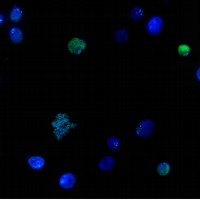

Epigenetics emerged on the scene in the 1990s. Researchers discovered that chromatin, the complex formed by DNA and histones, -proteins that bind strongly to DNA, thereby packaging it in chromosomes-, regulate gene expression. This additional layer of regulatory instructions, which are not held in DNA, comprise the epigenetic code.

Epigenetic differences explain, for example, why two cloned organisms are not the same or why twins develop illnesses of distinct genetic origin. Epigenetic studies promise not only to have a direct impact on health and our understanding of the relations between the environment and genetics but also to provide an explanation of basic aspects of cell biology. The co-organiser of the conference, Ferran Azorín, head of the “Chromatin Structure and Function” group at IRB Barcelona, comments that “deciphering and understanding the epigenome will shed light on fundamental processes in cell physiology. This knowledge will improve our understanding of the development of tumours and other diseases, and may lead to the design of new treatments for these conditions”. A new family of epigenetic drugs, designed to reverse the changes in the epigenome that occur during the development of several kinds of cancer, is currently available. Several of these pharmacological agents are now being used to treat some types of leukaemia and breast cancer.